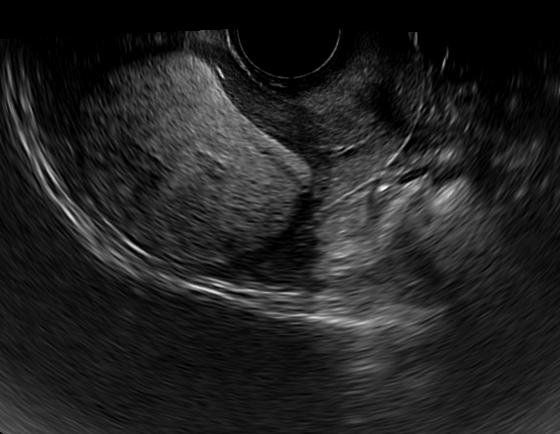

This is a confirmed case of scar ectopic pregnancy. Yesterday, I carried out this exam in an emergency room, without much time to perform an adequate sonogram, the patient did not feel good with “cramps” but no signs of bleeding.